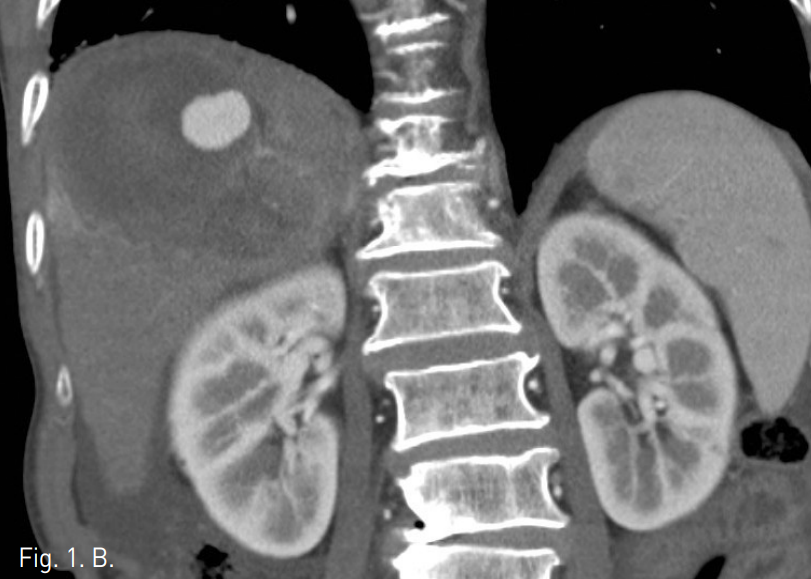

외래에서 시행한 복부 CT에서 간 우엽에 간동맥과 연결성을 보이는 2.5cm 크기의 가성 동맥류가 관찰되며 주위에 9cm 크기의 혈종이 있음. 간경변증을 보이고 있으나 간내에 간세포암종을 시사할만한 비정상적으로 조영증강되는 종괴의 소견은 관찰되지 않음(Fig. 1). 복부 MR에서 혈종의 뒤 안쪽으로 3.5cm 크기의 간세포암종으로 생각되는 병변이 관찰됨(Fig. 2).

Fig. 2

Axial T2-weigh ted MR image shows high density hematoma and adjacent hepatoma (arrow).